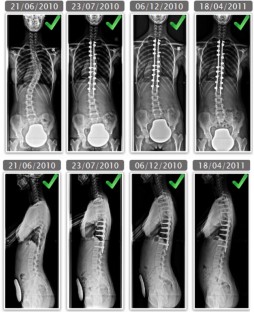

Clinical and radiological data were extracted from a prospective database of 132 AIS patients and 52 AS before and at last follow-up after surgical correction. Sagittal parameters were evaluated on AP and lateral radiographs using a custom software: pelvic incidence (PI), sacral slope (SS), pelvic tilt (PT), lumbar lordosis (LL), thoracic kyphosis (TK), C7 Barrey’s ratio, spino-sacral angle (SSA). A new algorithm of combination of balance parameters was proposed to characterize and compare the various pathological spino-pelvic settings. Based on PI subdivision in high (<55°) and low values (>55°), then on a range of PT indexed on PI giving the pelvis positioning (anteverted, normal or retroverted), the population was finally characterized by the C7 plumbline position with regard to the posterior edge of the sacrum and the center of the femoral heads, in balanced, slightly unbalanced and unbalanced. More specifically, the AIS study included the cervical shape alignment with cervical lordosis (CL) and sagittal thoracic profile assessment (hypo vs. normokyphotic). In AS, the study focused on thoraco-lumbar kyphosis (TLK) occurrence (LL length). Paired Student t tests were used for comparison (α = 0.02).

Results

Pre-operatively, in AIS there was a prevalence of lower PI (57 %). Whatever the PI, PT remained anteverted or normal. Positioning of C7 was much more unbalanced, forward of the femoral heads (50 %), than in asymptomatic population (17 %). There was a notable loss and reversal of cervical lordosis in the majority of subjects, with an average cervical kyphosis measurement of 10 ± 18°. Thoracic kyphosis values were lower than average, while lumbar lordosis values were within normal limits. After surgery, in the entire group, a slight but significant increase of PT coupled to a decrease of SS and LL was noted, while no changes could be documented in thoracic kyphosis and cervical lordosis. However, when sub-classified according to thoracic hypo versus normokyphosis pre-op, there was a significant decrease of TK coupled to a decrease of LL and CL in the normokyphotic group, while TK and CL were improved in the hypokyphotic group. A significant number of patients improved their global balance. Changes in sagittal profile between Lenke curve types were minimal. In AS there were significant differences between low and high PI populations. Severity of unbalance increased in high PI population with association of retroverted pelvis and forward unbalance. In lower PI, increasing PT was generally sufficient to balance the patients. The occurrence of TLK was strongly increased in the entire population and became the rule in those with lower PI (76 %). Post-operatively, in those with high PI, PT did not change while global balance improved slightly. The strategy of correction in higher PI was to maintain TLK. In those with low PI, PT improved while C7 did not change. Correction of TLK was obtained in eight cases.